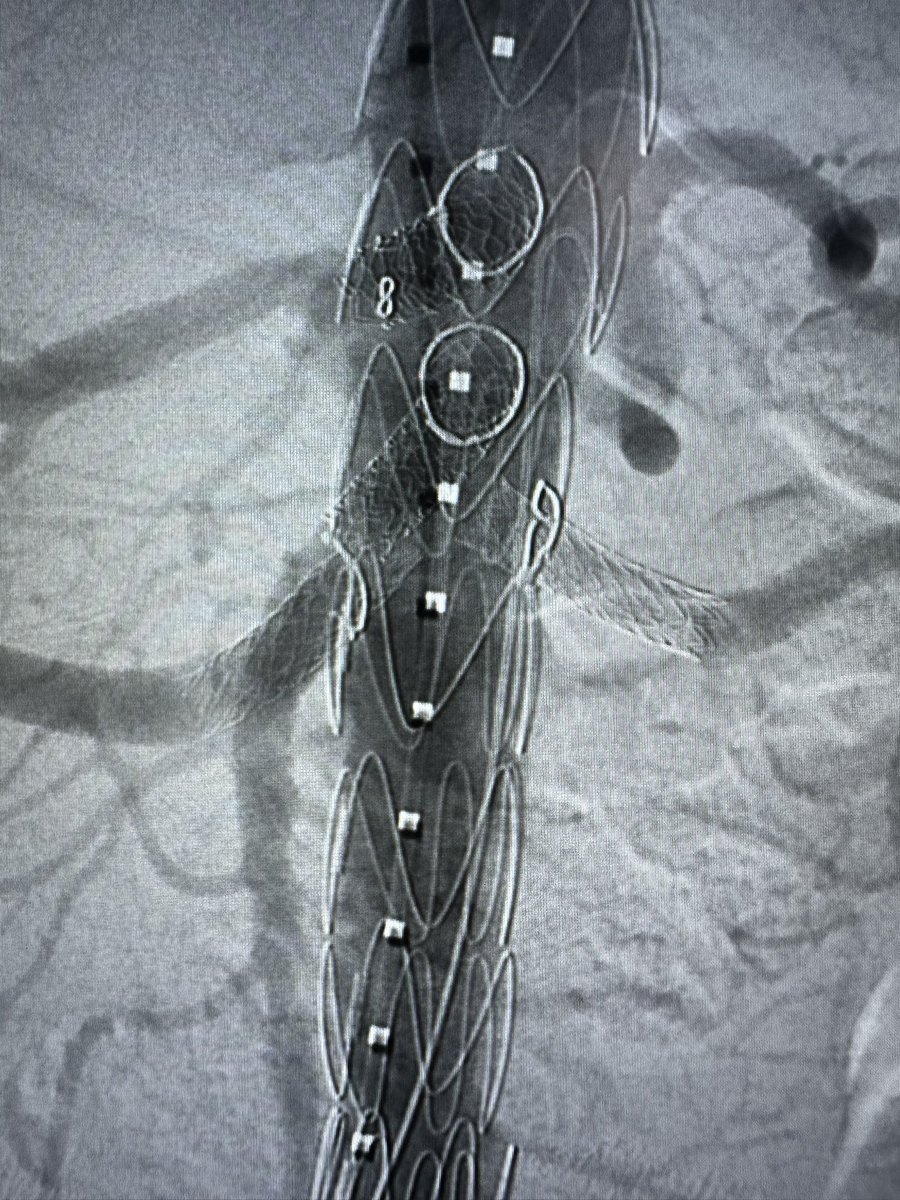

FEVAR with Diameter Reducing Ties plus 4 preloaded through-and-through wires for a small lumen case. Access from above. #AortaEd @gracemulatti @paulomenezesf @cfbechara @fonseca_alan5 @AndrePoci